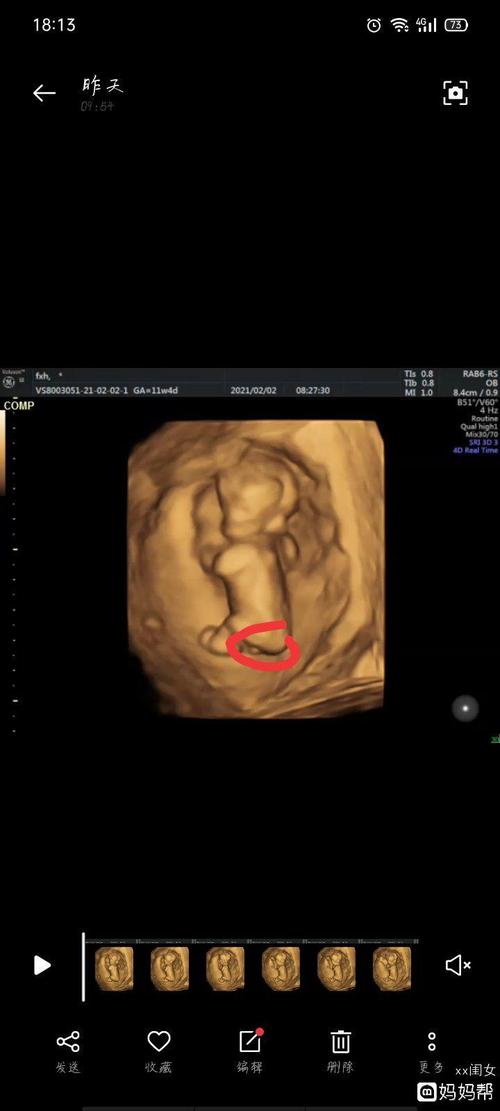

男女nt图对比,女宝nt图片

nt归来,有会看男女的亲吗?

nt过了,能看男女吗

nt nub点看男女_nt检查_女宝_母婴_孕产经验

附一张nt数据有会看男女的嘛头胎男女

NT图看男女

nt看男女

NT图如何看男女

nt图弯着就是男孩

孕13周nt男孩图

已生男孩的nt图片

怀男孩nt报告图片